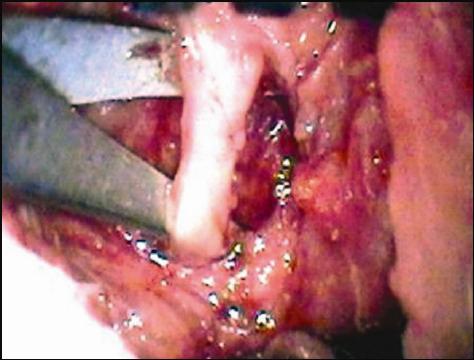

(Fig.1).

FIGURA 1: Animal na mesa operatória para cirurgia em nervo facial esquerdo.